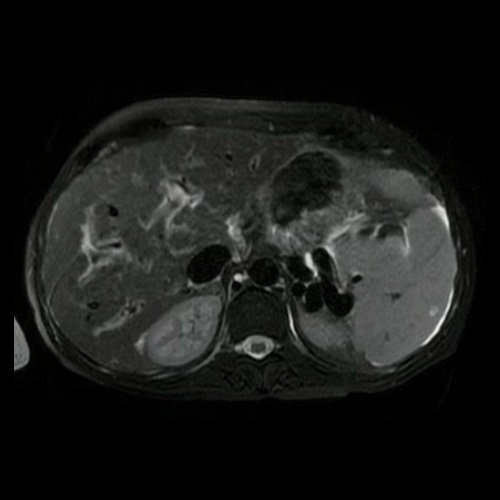

• Resonancia de abdomen y pelvis con contraste endovenoso (08/06/25): se interpreta en comparación con tomografía de enero de 2025. El examen realizado muestra el hígado de tamaño conservado, con intensidad de señal finamente heterogénea en forma difusa, no identificándose lesiones nodulares focales hepáticas. Se menciona la vena porta de calibre y flujo respetado, con signos de edema periportal difuso. Existe esplenomegalia, con una pequeña imagen quística subcapsular posterior. Prominentes estructuras vasculares venosas dilatadas, con la presencia de shunts esplenorrenales, ya estaban presentes en la TAC previa. No se identifican alteraciones focales en el páncreas, glándulas suprarrenales y riñones. Se menciona ascitis de mayor magnitud que en el estudio previo, se observa líquido perihepático, periesplénico y hacia las goteras parietocólicas, como así también líquido libre en la pelvis. Existen también estructuras ganglionares en el hilio hepático y en el hiato de Winslow, la de mayor tamaño mide 14 mm en el eje menor, entre la vena cava y la vena porta. Ya estaban presentes en la TAC previa. Bazo accesorio. Se visualiza parcialmente al colon, impresionando persistencia del engrosamiento parietal del colon ascendente, mencionado en la TAC previa, que si bien podría tener origen inflamatorio, sugiero estudio dirigido. El examen de la pelvis muestra al útero en AVF, el miometrio es heterogéneo a expensas de áreas de adenomiosis, y un mioma intramural anterior de 7 mm. La cavidad endometrial es lineal. El cérvix es prominente, no obstante se observa hipointenso en T2, no se identifican lesiones focales, la hipointensidad de señal, sugiere fibrosis, no obstante deberá cotajarse con antecedentes. El OCI y el canal endocervical se observan respetados por esta metodología. No se observan focos de restricción en difusión a nivel del cérvix uterino. Si la clínica lo justifica, sugiero cotejar con papanicolao y estudio directo. Se observan estructuras varicosas hacia ambos parametrios a predominio izquierdo. La vagina muestra espesor parietal respetado. Existe ascitis interasas, en la pelvis y hacia el fondo de saco de Douglas. Los ovarios se encuentran en proyección habitual, no identificándose lesiones focales anexiales. Vejiga de paredes finas sin lesiones endoluminales. No se observan adenomegalias en cadenas ilíacas o inguinales. No se identifican lesiones óseas en la pelvis.

RMI de abdomen Corte axial (08/06/25)